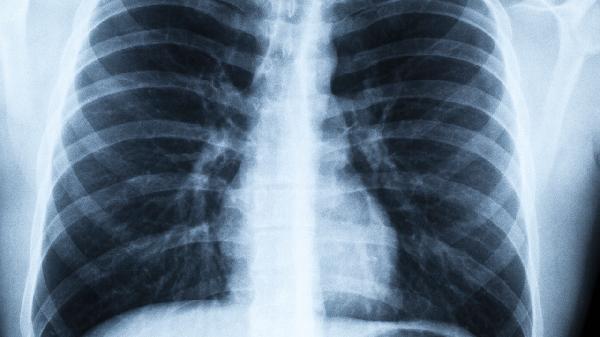

2、影像学检查结果

PET-CT显示病灶完全消失,且半年内复查无新增代谢活跃灶,说明治疗效果理想。普通CT显示原发灶周围无异常增大的淋巴结也很重要。